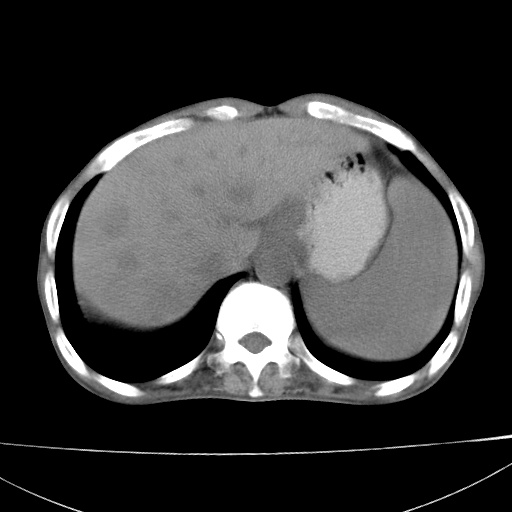

患者 男  41岁,右上腹痛伴腹泻10天,8年前有乙肝,本次b超查肝右叶占位来做ct ,请会诊!

肝硬化\\脾大\\门静脉高压,胃底静脉曲张可能性大.肝右叶肝癌肝内转移,建议增强.左侧小结石.

肝右叶肝癌肝内转移,建议增强

支持肝癌伴肝内转移,脾大,门静脉高压,胃底静脉曲张。

1)考虑肝癌;建议行ct增强扫描检查。2)脾大,门静脉高压,胃底静脉曲张。3)左肾小结石。

1)考虑肝癌及门脉瘤栓,建议行ct增强扫描检查。2)脾大,门静脉高压,胃底静脉曲张。3)左肾小结石。

结合病史;考虑肝癌。门静脉高压,脾大。胃底静脉曲张。

1)考虑肝癌;2)脾大,门静脉高压,胃底静脉曲张。3)左肾小结石。建议行ct增强扫描检查。